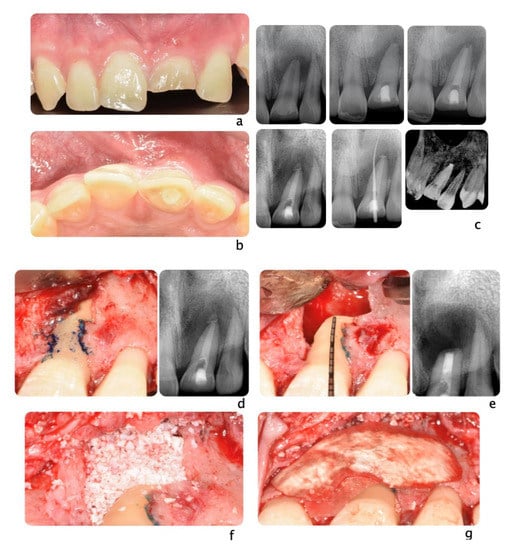

Figure 3.

A 20-year-old Asian male had #8 diagnosed with a root fractured due to sport related trauma (a). The tooth was endodontically treated, followed by healing with interposition of connective tissue (b). After healing was completed, a second sport injury involved the same tooth. The tooth mobility increased, and a periodontal lesion was diagnosed by elevated probing depth. The tooth was stabilized with orthodontic wire and patient was referred to periodontist for evaluation. Combined with malocclusion and anterior open-bite, the treatment plan was made as full-month orthodontics and auto-transplantation of #28. Tooth #8 and 28 were extracted (c,d) and a premolar replica was printed (d). After socket adjustment with the replica (e), tooth #28 was stabilized in place with sutures (f). After periodontal stabilization and verification of periodontal healing (g), the final restoration was delivered (h).